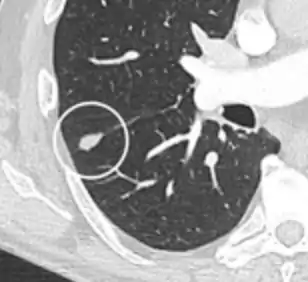

- Pleural retraction is far more common in cancers.[9] It is the pulling of visceral pleura towards the nodule.[9]

Nodule with pleural retraction.[9]

In this case, pleural retraction is seen as a triangular fat component.[9]